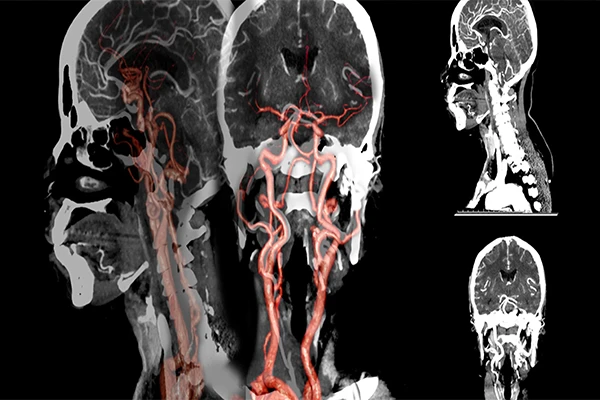

A Guide to CT Angiography (CTA): Visualizing Blood Vessels

Learn how CTA uses IV contrast and precise timing to create detailed 3D images of arteries and veins.